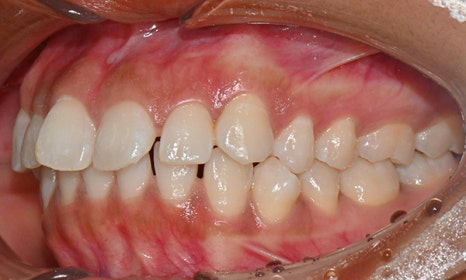

교정 마무리 후 사진 (2025.8)

최종적으로 교정을 마무리한 후에는

위아래 치아 배열이 훨씬 가지런해졌고,

깊게 물렸던 과개교합도 크게 개선되었어요.

왼쪽 작은 어금니는 목표에서 제외했던 만큼,

아직 완벽하게 교합이 맞지는 않았지만,

치료 자료를 전달해 드리고 추후 본국으로 돌아가서

남은 치료를 이어서 받기로 하셨답니다.

한 가지 더:

오른쪽 위 앞니는

원래도 잇몸이 조금 내려가 있었어요.

그래서 교정을 끝내면 좌우 잇몸 높이가

다를 수 있다는 점을 미리 말씀드렸고요.

나중에 치은성형술로 잇몸 높이를 맞추면

더 예뻐 보일 거라고 추천해 드렸어요.